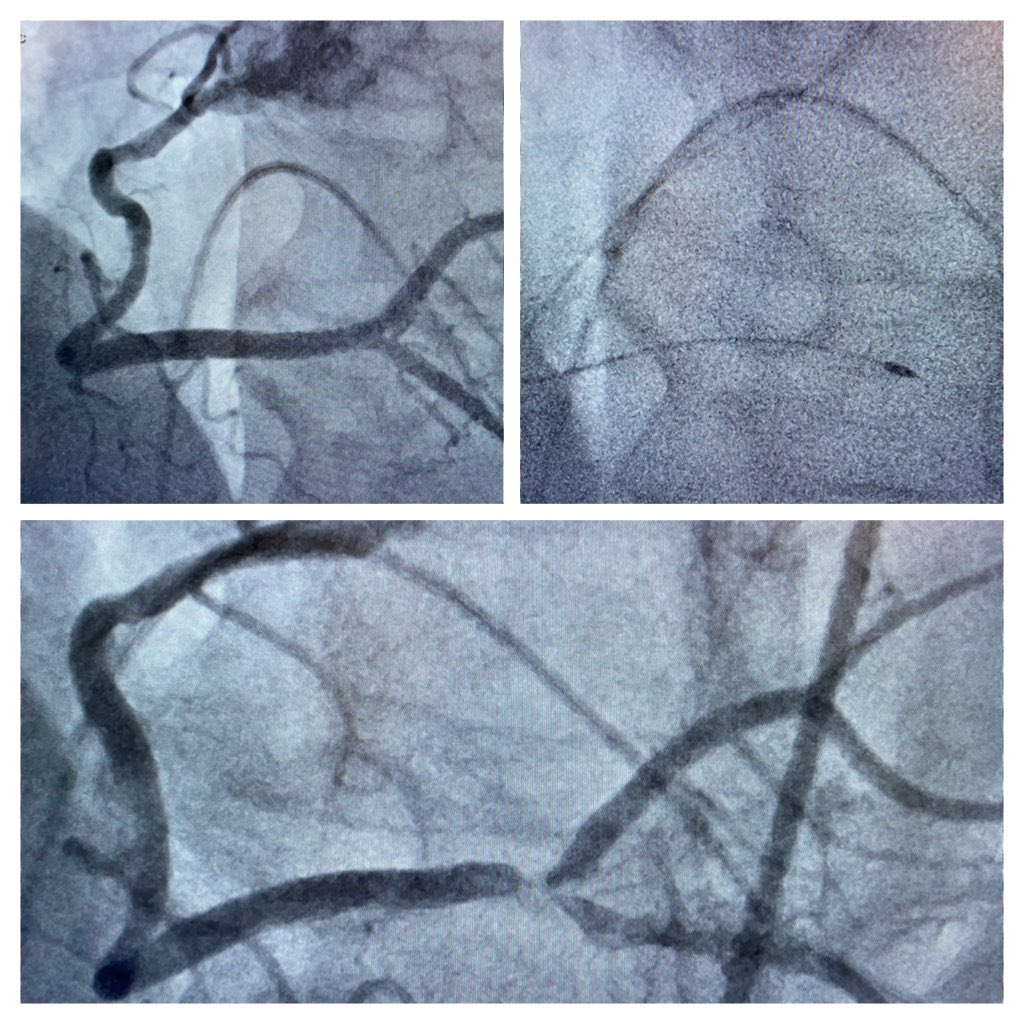

RCA stenosis Medina 1-1-1. Fielder XT-R, Supercross FT, Rotapro 1,25 mm. NSE Alpha 3,0/13 mm. TAP with Xience ProS 3,0 23 mm in RCA/RIVP and 3,0/18 mm in RPLS. Final KB. POT with Sapphire NC 24 4,0/8 mm. @BotPci #Rotapro @Obisht @KPujdak @KardiologieHH @klinki_hh @VRubesch

AndWierucki's tweet image. RCA stenosis Medina 1-1-1. Fielder XT-R, Supercross FT, Rotapro 1,25 mm. NSE Alpha 3,0/13 mm. TAP with Xience ProS 3,0 23 mm in RCA/RIVP and 3,0/18 mm in RPLS. Final KB. POT with Sapphire NC 24 4,0/8 mm. @BotPci #Rotapro @Obisht @KPujdak @KardiologieHH @klinki_hh @VRubesch